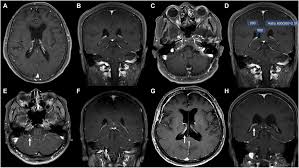

Morphology and evolution of cortical lesions in multiple sclerosis.

Owing to its ability to depict the pathologic features of multiple sclerosis (ms) in exquisite detail, conventional magnetic resonance (mr) imaging has become an established tool in the diagnosis of this disease and in monitoring its evolution. According to the mcdonald criteria for ms, the diagnosis requires objective evidence of lesions disseminated in time and space. Widespread use of mri (magnetic resonance imaging) has revolutionized the ability to diagnose multiple sclerosis. 39 calabrese m, filippi m, rovaris m et al. Magnetic resonance imaging (mri) is a noninvasive type of imaging test that healthcare professionals use to detect multiple sclerosis (ms) activity in the brain and spinal cord. Mri is an important diagnostic tool for multiple sclerosis because it produces images of lesions in the brain and spinal cord. In fact, researchers and medical professionals consider mri to be one of the biggest breakthroughs in the field of multiple sclerosis, since it makes it possible to see lesions on the brain and spinal cord. The diagnosis is made from a combination of clinical, imaging, and laboratory findings patients with ms can present with motor, sensory, visual, and/or autonomic pathway symptoms Mri and ms multiple sclerosis (ms) is a condition in which the body's immune system attacks the protective covering (myelin) surrounding the nerves of the central nervous system (cns). Morphology and evolution of cortical lesions in multiple sclerosis. Since its technical development in the early 1980s, magnetic resonance imaging (mri) has quickly been adopted as an essential tool in supporting the diagnosis, longitudinal monitoring, evaluation of therapeutic response, and scientific investigations in multiple sclerosis (ms). Abnormalities show up on scans from many illnesses other than ms. Magnetic resonance imaging (mri) is one of the most important and most commonly used tools for diagnosing and monitoring multiple sclerosis (ms).

Brain mri scan showing multiple sclerosis lesions. Widespread use of mri (magnetic resonance imaging) has revolutionized the ability to diagnose multiple sclerosis. 39 calabrese m, filippi m, rovaris m et al. In fact, researchers and medical professionals consider mri to be one of the biggest breakthroughs in the field of multiple sclerosis, since it makes it possible to see lesions on the brain and spinal cord. Multiple sclerosis and mri 3.05.19 although the cause of multiple sclerosis (ms) is unknown ongoing research is moving forward at a remarkable pace and more potential therapies appear to be in the pipeline than ever before.

Since its technical development in the early 1980s, magnetic resonance imaging (mri) has quickly been adopted as an essential tool in supporting the diagnosis, longitudinal monitoring, evaluation of therapeutic response, and scientific investigations in multiple sclerosis (ms). Morphology and evolution of cortical lesions in multiple sclerosis. Magnetic resonance imaging (mri) is one of the most important and most commonly used tools for diagnosing and monitoring multiple sclerosis (ms). Magnetic resonance imaging (mri) plays a crucial role in multiple sclerosis (ms) diagnosis, disease monitoring, prognostication, and research. The clinical usage of … Brain mri scan showing multiple sclerosis lesions. An mri scan is the best way to locate multiple sclerosis (ms) lesions (also called plaques) in the brain or spinal cord. Magnetic resonance imaging (mri) has developed into the most important tool for the diagnosis and monitoring of multiple sclerosis (ms).

Brain mri scan showing multiple sclerosis lesions multiple sclerosis. Multiple sclerosis and mri 3.05.19 although the cause of multiple sclerosis (ms) is unknown ongoing research is moving forward at a remarkable pace and more potential therapies appear to be in the pipeline than ever before.